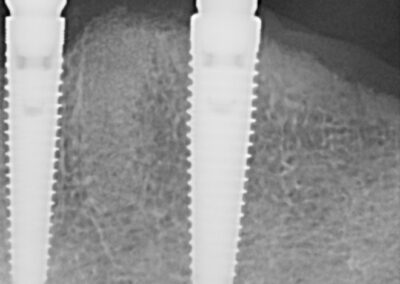

This is a wonderful case of a patient who had broken teeth for a very long time. The outcome is a supported set of full dentures on implants. The patient does not experience movement of teeth and has the ability to eat all food. The implant supported denture allows the patient to have a very high biting force, which is very important when you want to eat crunchy fresh fruits and vegetables. This was a fully guided case.